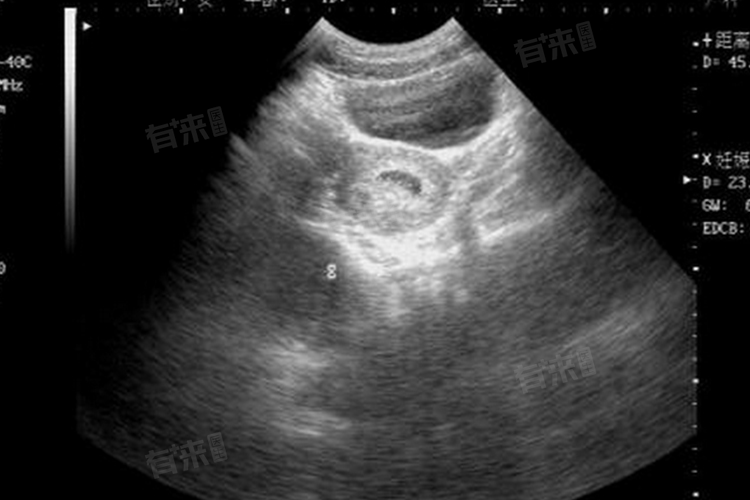

- 刚怀孕时,妇科检查可以确认是否怀孕,以及怀孕周期、孕囊的着床位置、胎儿的发育情况等。如果孕妇患有盆腔炎、宫颈炎、阴道炎等疾病,也可以在妇科进行检查和治疗。

- 产科主要负责孕妇的产前检查、分娩和产后护理等工作。产科检查包括腹部超声、血HCG、尿常规等,以了解胎儿的生长和发育情况。

- 建议在停经45天左右去医院做详细的检查,包括化验绒毛膜促性腺激素、孕酮,以及进行超声检查等。由于不同医院的规定可能有所不同,建议在前往医院之前先咨询医院的咨询台或挂号窗口,了解具体的挂号流程和科室设置。